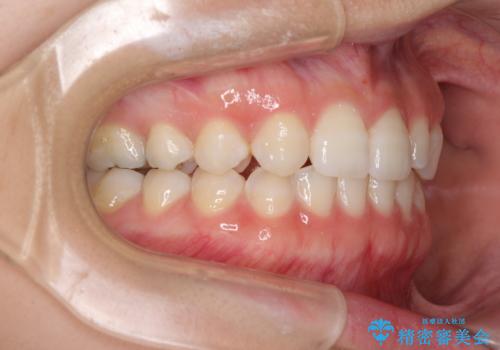

- 1年後に海外に転居するため、気になる前歯を矯正治療で整えたいとのことで来院された患者様です。

下顎は叢生が強かったため、奥歯までワイヤーを装着し、上顎は前歯の一部のみ気になっていたので、その部分にだけワイヤー装置を装着することとしました。